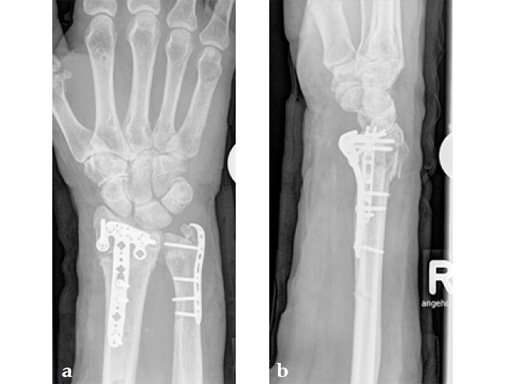

Fig 1ab Preoperative x-rays.